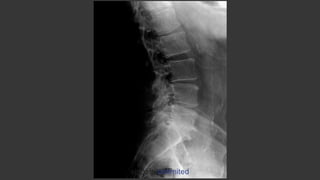

Investigation

• Xray

• MRI

• CT myelogram

• EMG, SSEPs, NCS